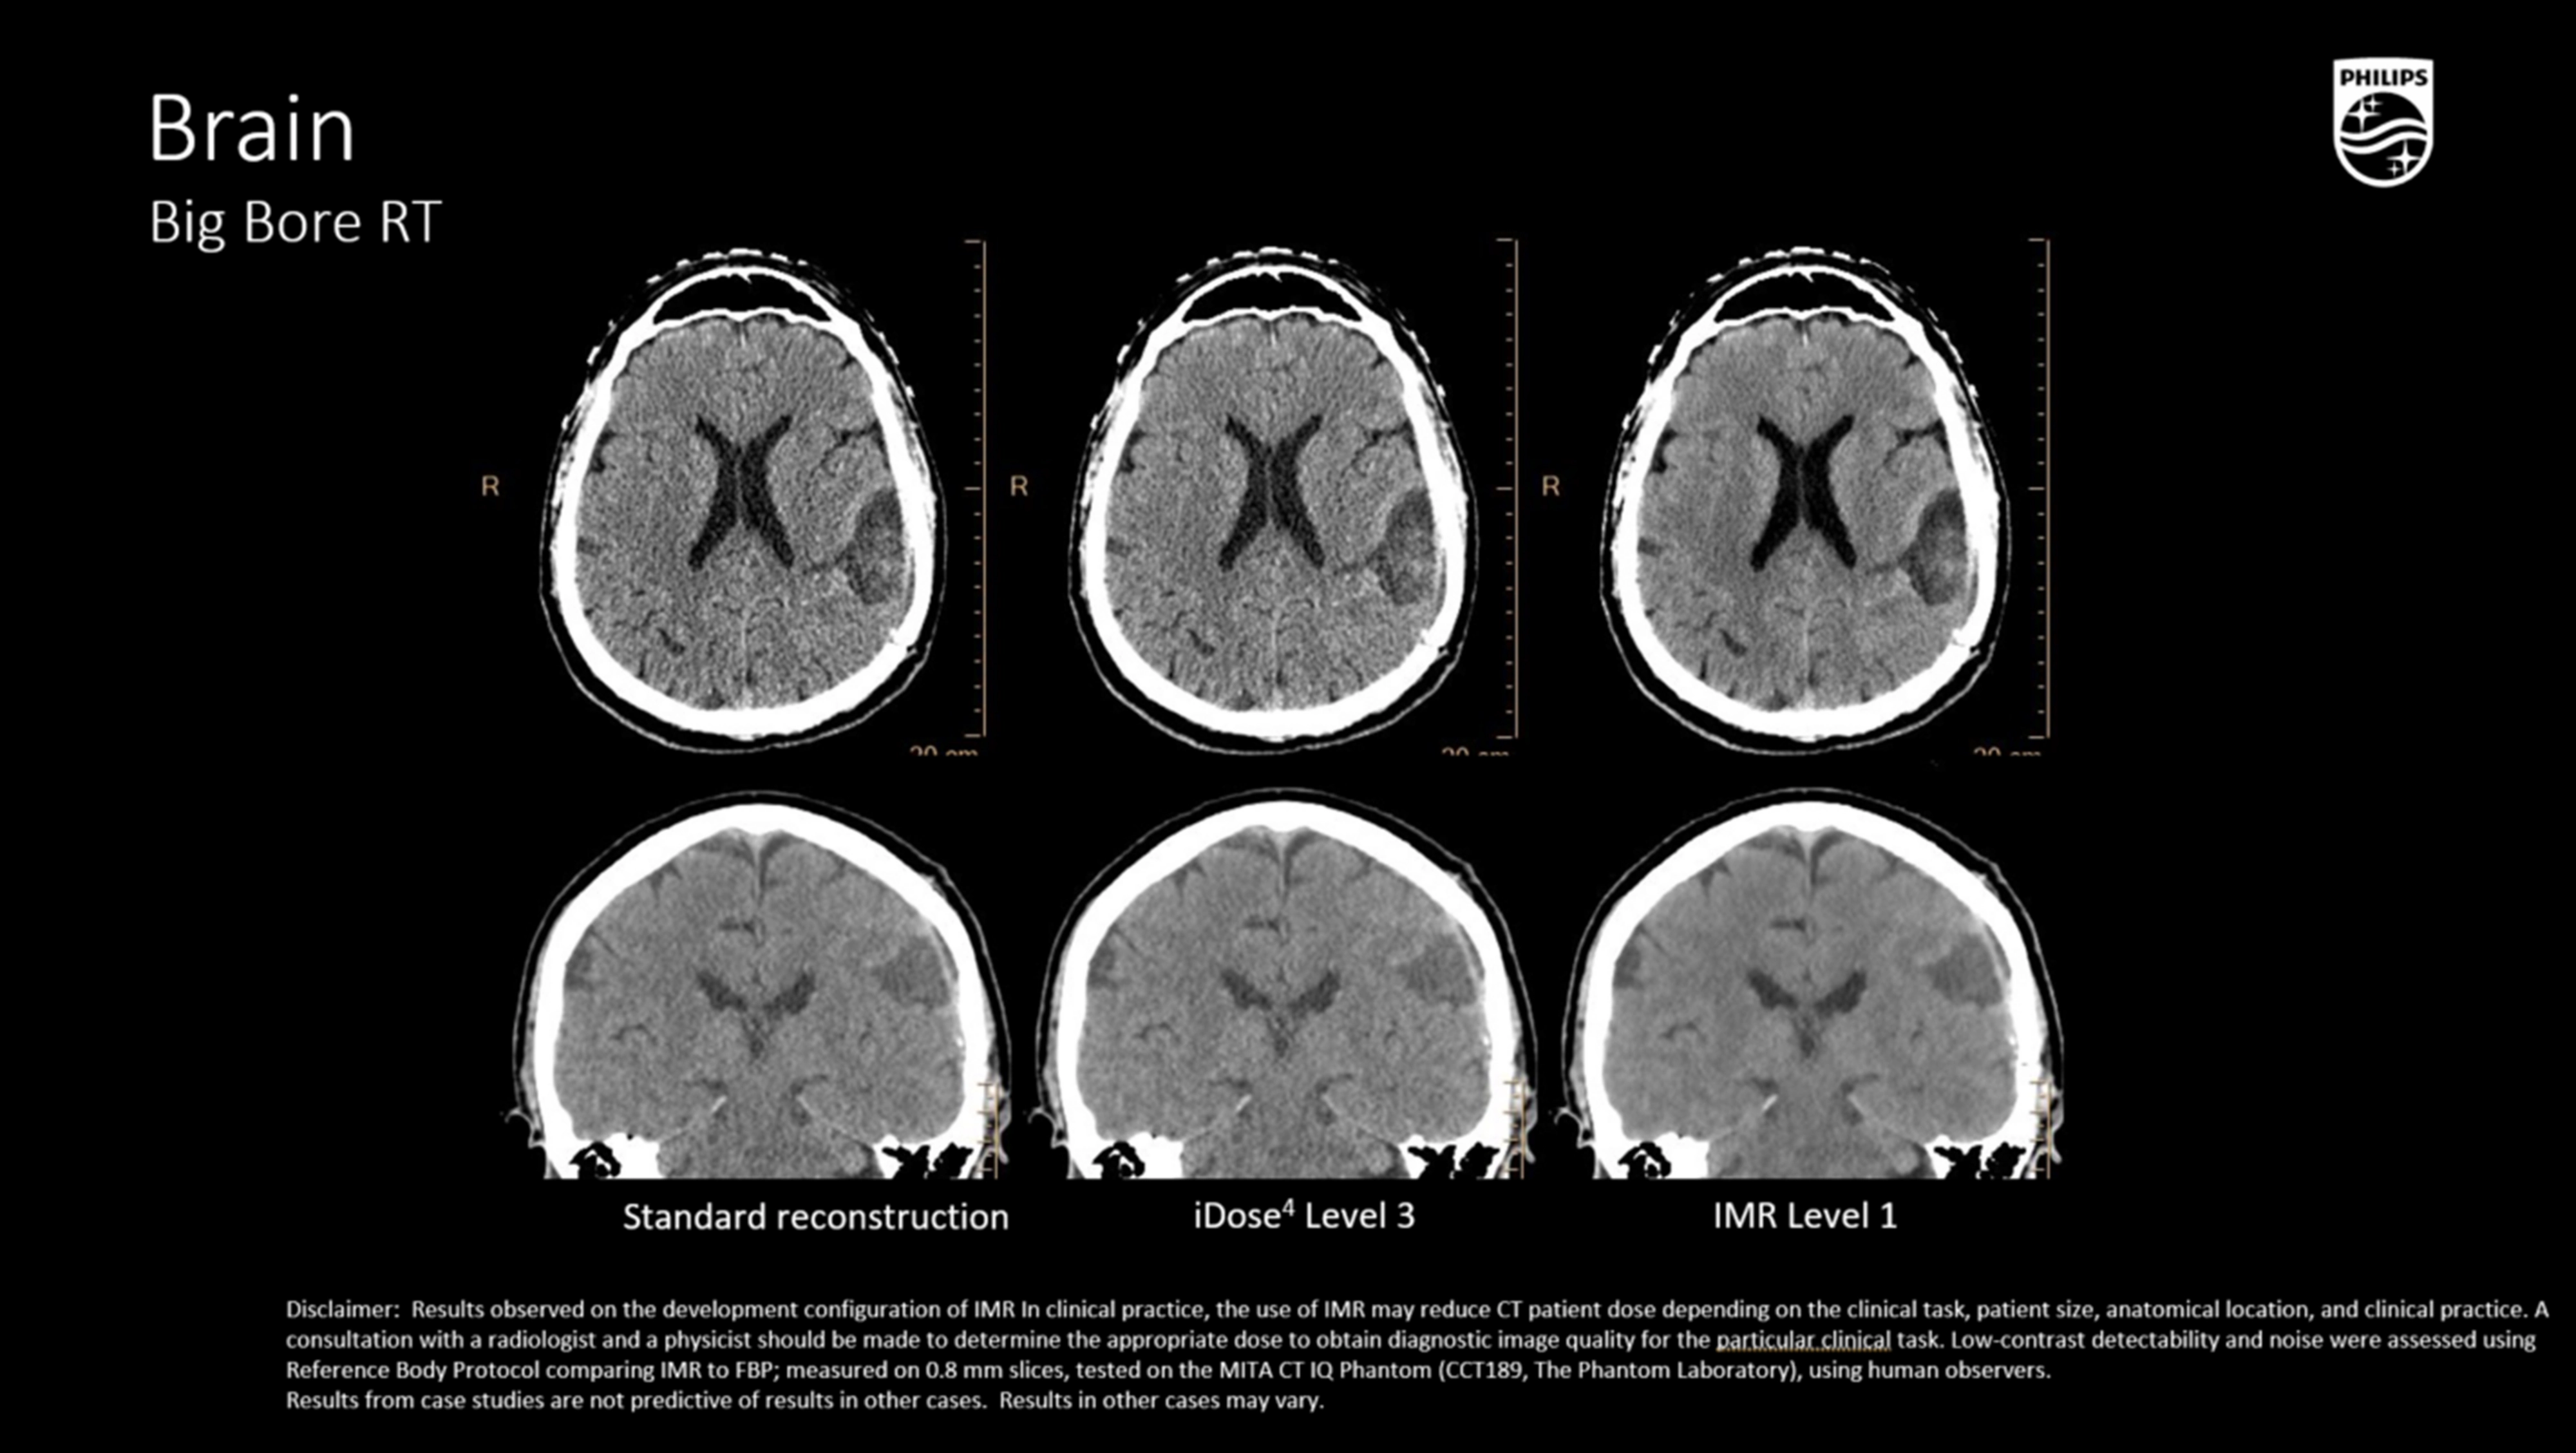

iDose⁴ (Iterative Dose Reduction Technology)

- Гибридная итеративная реконструкция в проекционном и изображен ческом пространстве повышает качество изображения и устраняет артефакты.

- Повышает контрастно-шумовое соотношение (CNR), снижая лучевую нагрузку на 50–80% при сохранении пространственного разрешения

- Поддержка низкокиловольтных протоколов (100/80 кВ), актуальна при планировании в педиатрии и у кахектических пациентов.

Неврология и краниоспинальные опухоли

- Высокоточная визуализация базальных ганглиев, хиазмы, спинного мозга,

- Применение в стереотаксическом планировании (SRS/SBRT),